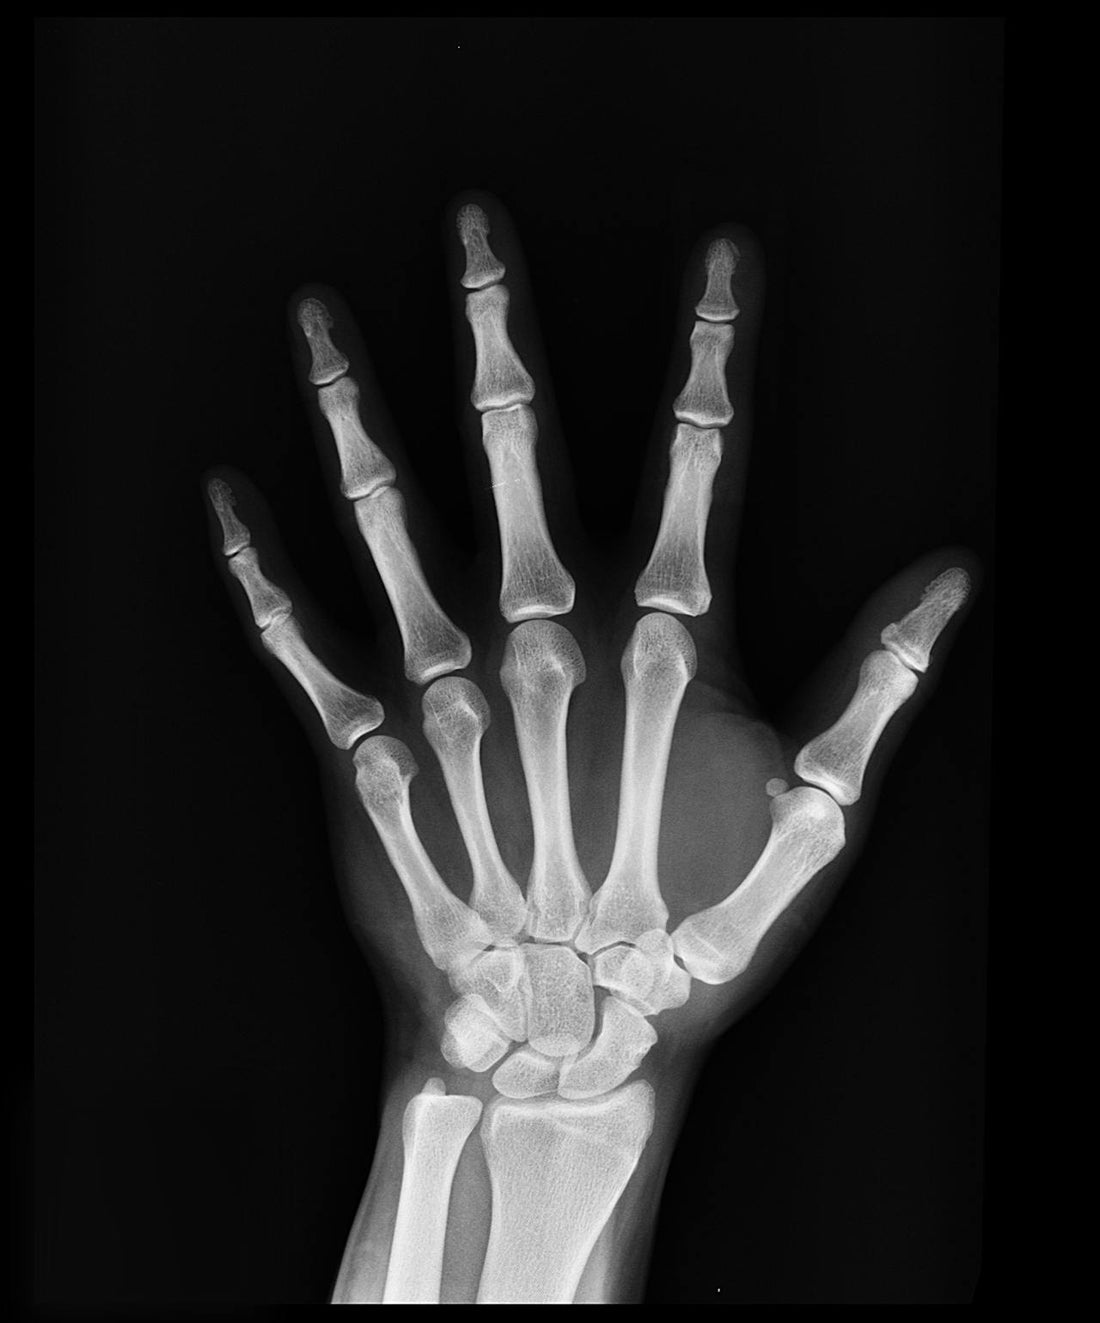

El crecimiento y desarrollo de los huesos durante la infancia son cruciales para asegurar una salud ósea sólida en la adultez. Los primeros años de vida son una etapa clave para establecer una base de huesos fuertes, y esto depende en gran medida de la alimentación y hábitos de vida saludables. En este artículo, exploraremos las mejores prácticas para promover una buena salud ósea en los niños.

Durante la niñez y la adolescencia, el cuerpo está en constante crecimiento, y una gran parte de ese desarrollo incluye el fortalecimiento de los huesos. Aproximadamente el 90% de la masa ósea máxima se alcanza en las primeras dos décadas de vida, por lo que es fundamental apoyar el crecimiento de los huesos desde temprana edad.

Contar con huesos fuertes en la infancia no solo previene fracturas y lesiones, sino que también reduce el riesgo de padecer enfermedades óseas como la osteoporosis en la vida adulta. Una buena densidad ósea lograda durante la niñez y la adolescencia puede ser la mejor defensa contra problemas óseos en el futuro.